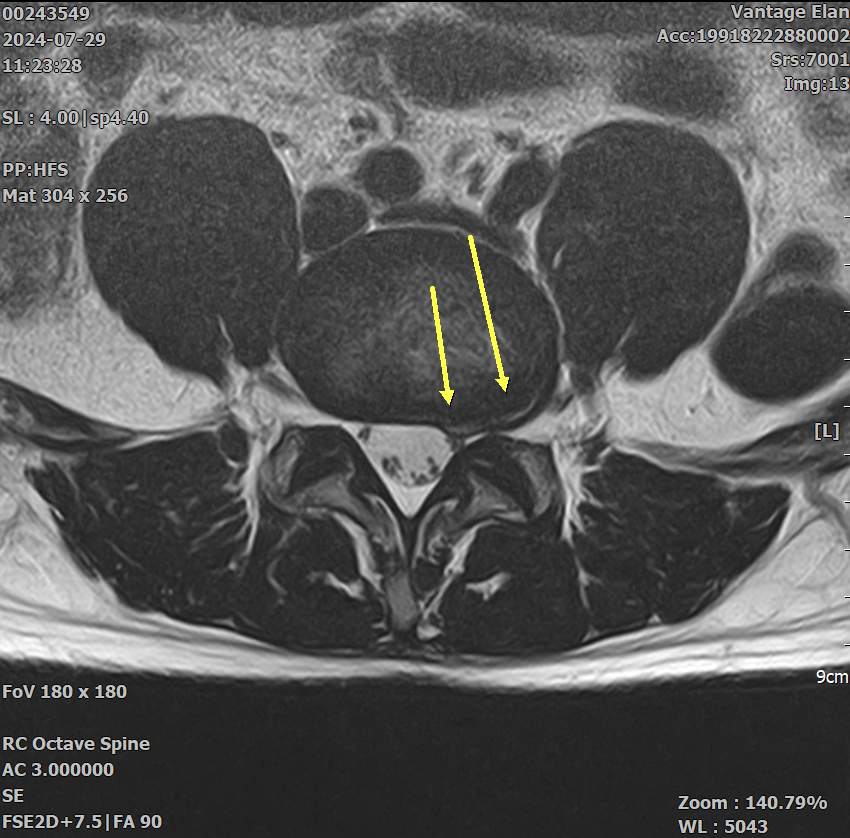

두가지 증상 때문에 요추와 골반 MRI 를 촬영하게 되었습니다.

저는 각기 다른 질환 (고관절충돌증후군과 척추관협착증) 을 의심하였는데 병원에서는 모두 허리디스크 퇴행으로 인한 것이라고만 설명해서 실제로 다른 가능성은 없는것인지 궁금하여 질문 남깁니다.

아래 영상 첨부하였지만.. 이정도 상태로 아래와 같은 두가지 증상이 생기는 것이 상식적인 이야기인지 궁금합니다. (골반 영상은 무엇을 첨부해야할지 몰라 첨부하지 않았지만 영상상으론 아무 문제 없다고 들었습니다.)

평상시에 1시간씩 빠른 속도로 걷는 것을 즐겨하고 산책도 좋아하는 편인데, 유독 느린 템포로 가다 서다 반복하는 경우에 시간이 얼마 지나지 않아 허리가 끊어질것 같은 느낌이 듭니다. 심하면 집을 나선지 30분도 안되어 통증이 발생하여 점점 심해집니다. 눕거나 쪼그려 앉으면 바로 증상이 바로 완화되고, 앉아서 등을 기대면 괜찮아지기도 합니다. (디스크로 인한 문제보다는 척추관협착증과 관련있지 않나 의심)

우선 mri와 질문하신 내용들을 종합해봤을때 증상으로는 충분히 고관절충돌증후군 또는 고관절활액막염이 의심이 가는 증상이고, 척추관협착증에서 나타나는 증상이기도 합니다 (빠른 시일내에 호전을 보이셨기에 이 부분은 확인 해보셔야 할것 같습니다).

다만 mri상 허리 척추 뼈와 뼈 사이의 공간은 협착증이 심해 보이진 않고 다만 퇴행성의 모습이 보이기도 합니다.